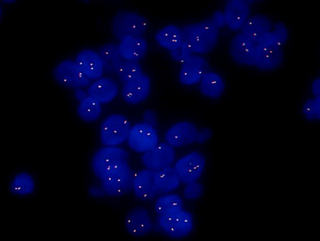

MF43-N+MSX11拍攝的FISH圖片

FISH樣品在紫外激發(fā)光的照射在,顯現(xiàn)出藍色的細胞輪廓的信號,在藍色激發(fā)光的照射下在細胞內(nèi)顯現(xiàn)出綠色的探針信號,在綠色激發(fā)光的照射下在細胞內(nèi)顯現(xiàn)出紅色的探針信號。